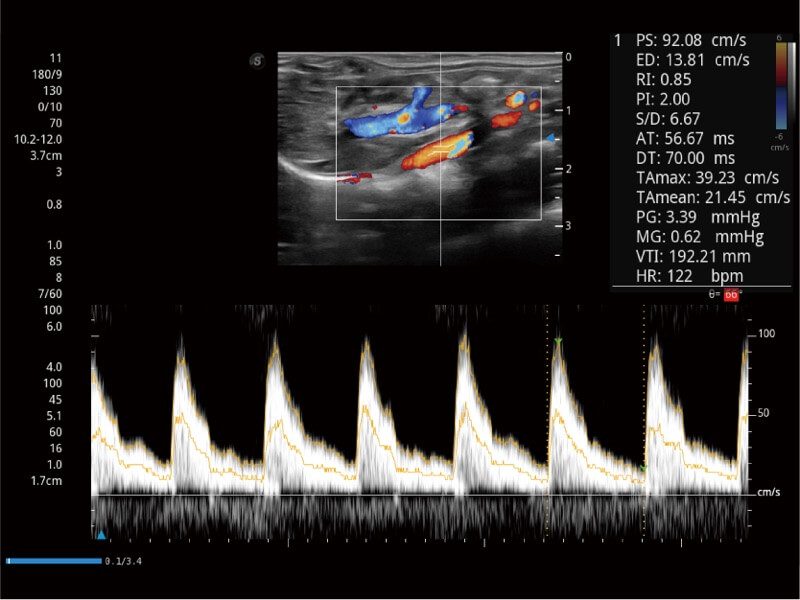

Ausgestattet mit dem gesamten Sortiment an Phased-Array-Schallköpfen von SonoScape (S1-5, 7P-A, 8P1), hochentwickelter Verarbeitungstechnologie und modernsten kardiologischen Tools bietet die ProPet-Serie Tierärzten eine umfassende ABklärung der Herz- und Myokardfunktionen.

Nutzt myokardiale Doppler-Frequenzverschiebungen zur Quantifizierung der myokardialen Gewebebewegung, wobei Rot und Blau die unterschiedlichen Bewegungsrichtungen der Herzwände darstellen. Durch die Kombination von TDI und PW lässt sich die Bewegungsbahn der Myokardwand besser erfassen.